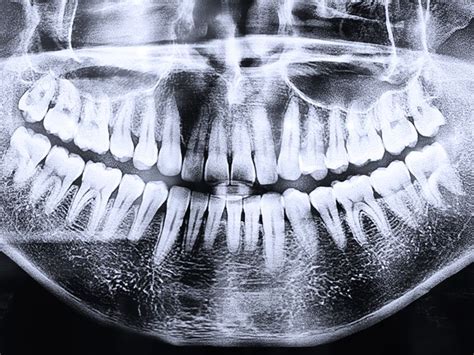

- Ortopantomografía: También llamada radiografía dental panorámica, es el tipo de radiografía dental más común. Muestra la totalidad de la estructura facial y mandibular (arcadas superior e inferior, huesos maxilares, mandíbula y estructuras de soporte).